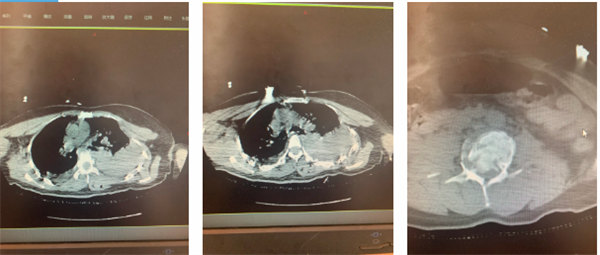

術前影像

骨一科團隊檢查后發現,患者腰椎爆裂性骨折 、胸椎爆裂性骨折、腰脊髓損傷伴下肢癱瘓、胸腰椎多發橫突骨折、胸腰椎多發棘突骨折、左側肩胛骨骨折、閉合性胸部損傷、肋骨多處骨折、胸骨骨折……按照常規治療流程,應于患者受傷后6至8小時行急診手術減壓、內固定,解除神經壓迫,重建脊柱穩定性。但由于患者一方面失血過多導致血壓不穩定;另一方面左側胸壁塌陷,雙側多處肋骨骨折,且腹部情況未完全查清;再者患者腰椎手術需俯臥位進行,手術體位或加重胸部損傷。同時多學科會診發現患者伴有嚴重創傷性血氣胸、創傷性濕肺、閉合性腹部損傷。